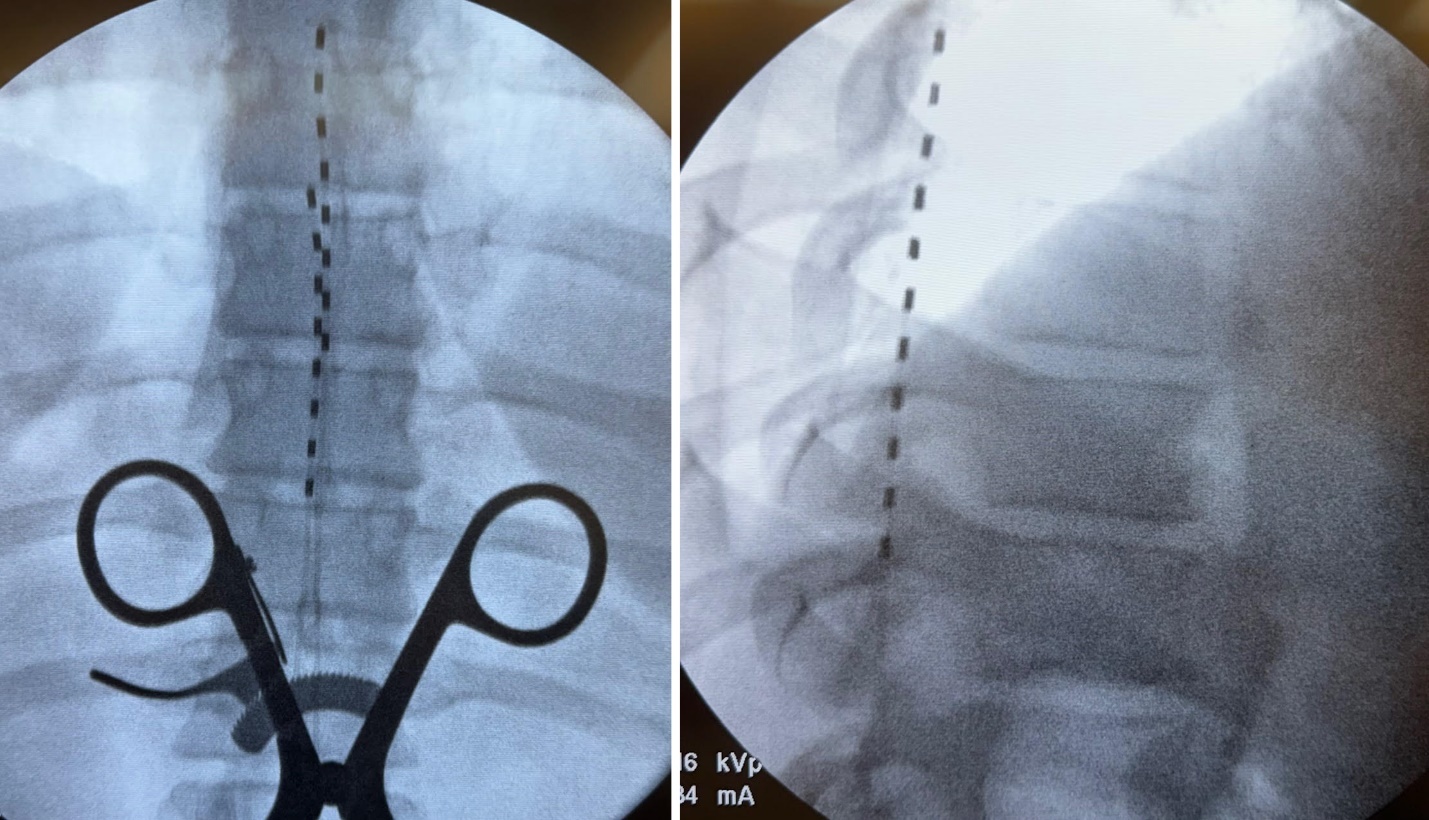

At follow-up after implantation, the patient continued to report >70% improvement in pain, further reduction in radicular symptoms, and enhanced functional mobility. She remained able to ambulate with a cane and had begun to walk independently for short distances. Her quality of life, mood, and overall activity level improved substantially. Images of the implant are shown below with one lead placed at the top of T7 with the second lead placed at the top of T8 slightly left of midline given her pain complaints (Figure 1).